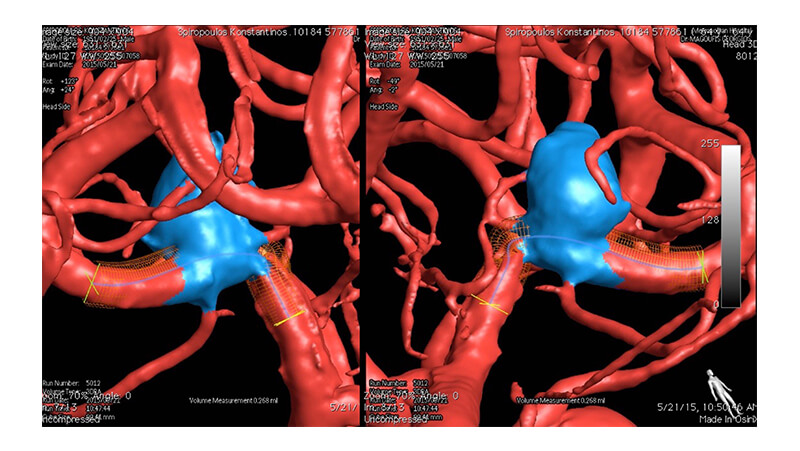

Εικόνα 2: Τρισδιάσταση ανασύνθεση εικόνων περιστροφικής ψηφιακής αγγειογραφίας. Φαίνεται ότι από την βάση του ανευρυσματικού σάκκου εκφύεται μετωπιαίος κλάδος. Η πλήρης απόφραξη του ανευρύσματος θα οδηγήσει σε απόφραξη του μετωπιαίου κλάδου. Αμέσως πριν το ανεύρυσμα, στο τελικό Μ1 τμήμα, διακρίνεται η τοπική στένωση της μέσης εγκεφαλικής αρτηρίας.